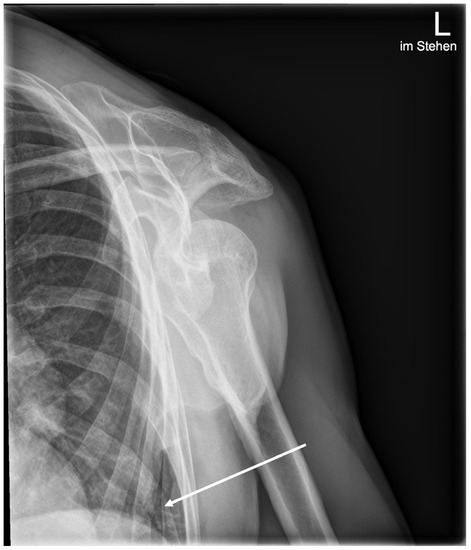

3.3. Sensitivity and Specificity by Anatomical Region